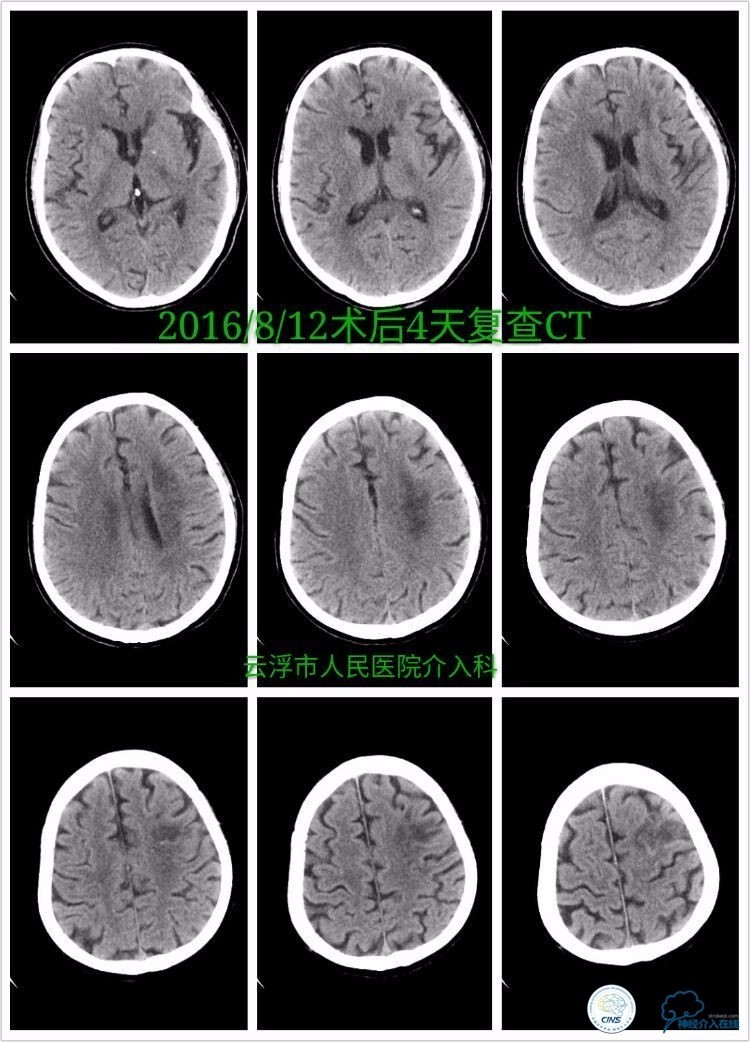

》术后第6小时复查颅脑CT:

》术后第四天颅脑CT:

术后第1周内观察患者认知、言语功能改善明显,右侧肢体肌力0级。

术后第3周观察患者部分混合性失语,右侧肢体上肢1级,下肢2级。